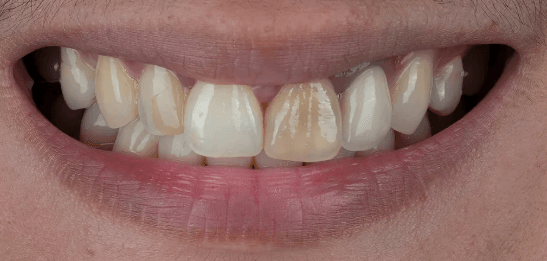

미아사거리 전체임플란트 전후

오랜 기간의 심한 치주염과 반복적 치아 파절로 통증·저작 장애가 심해진 환자분입니다. 보존 가능성을 충분히 평가한 뒤, 정밀 CT와 구강스캔을 바탕으로 상악 전체임플란트를 계획했습니다. 염증 치아를 단계적으로 정리하고 감염을 제어한 후 디지털 가이드로 안전하게 식립했습니다.

수술 과정에서 회복을 돕기 위해 자가혈/연어주사 등을 적용했고, 임시 보철로 적응 기간을 거친 뒤 최종 보철을 장착했습니다. 이후 정밀한 교합 조정으로 씹는 힘을 균형 있게 분산시켜 편안한 저작과 자연스러운 발음을 확보했습니다. 현재 환자분은 일상 식사가 한결 편해졌으며 심미적으로도 만족도가 높습니다. (개인 상태에 따라 계획·기간·결과는 달라질 수 있습니다.)